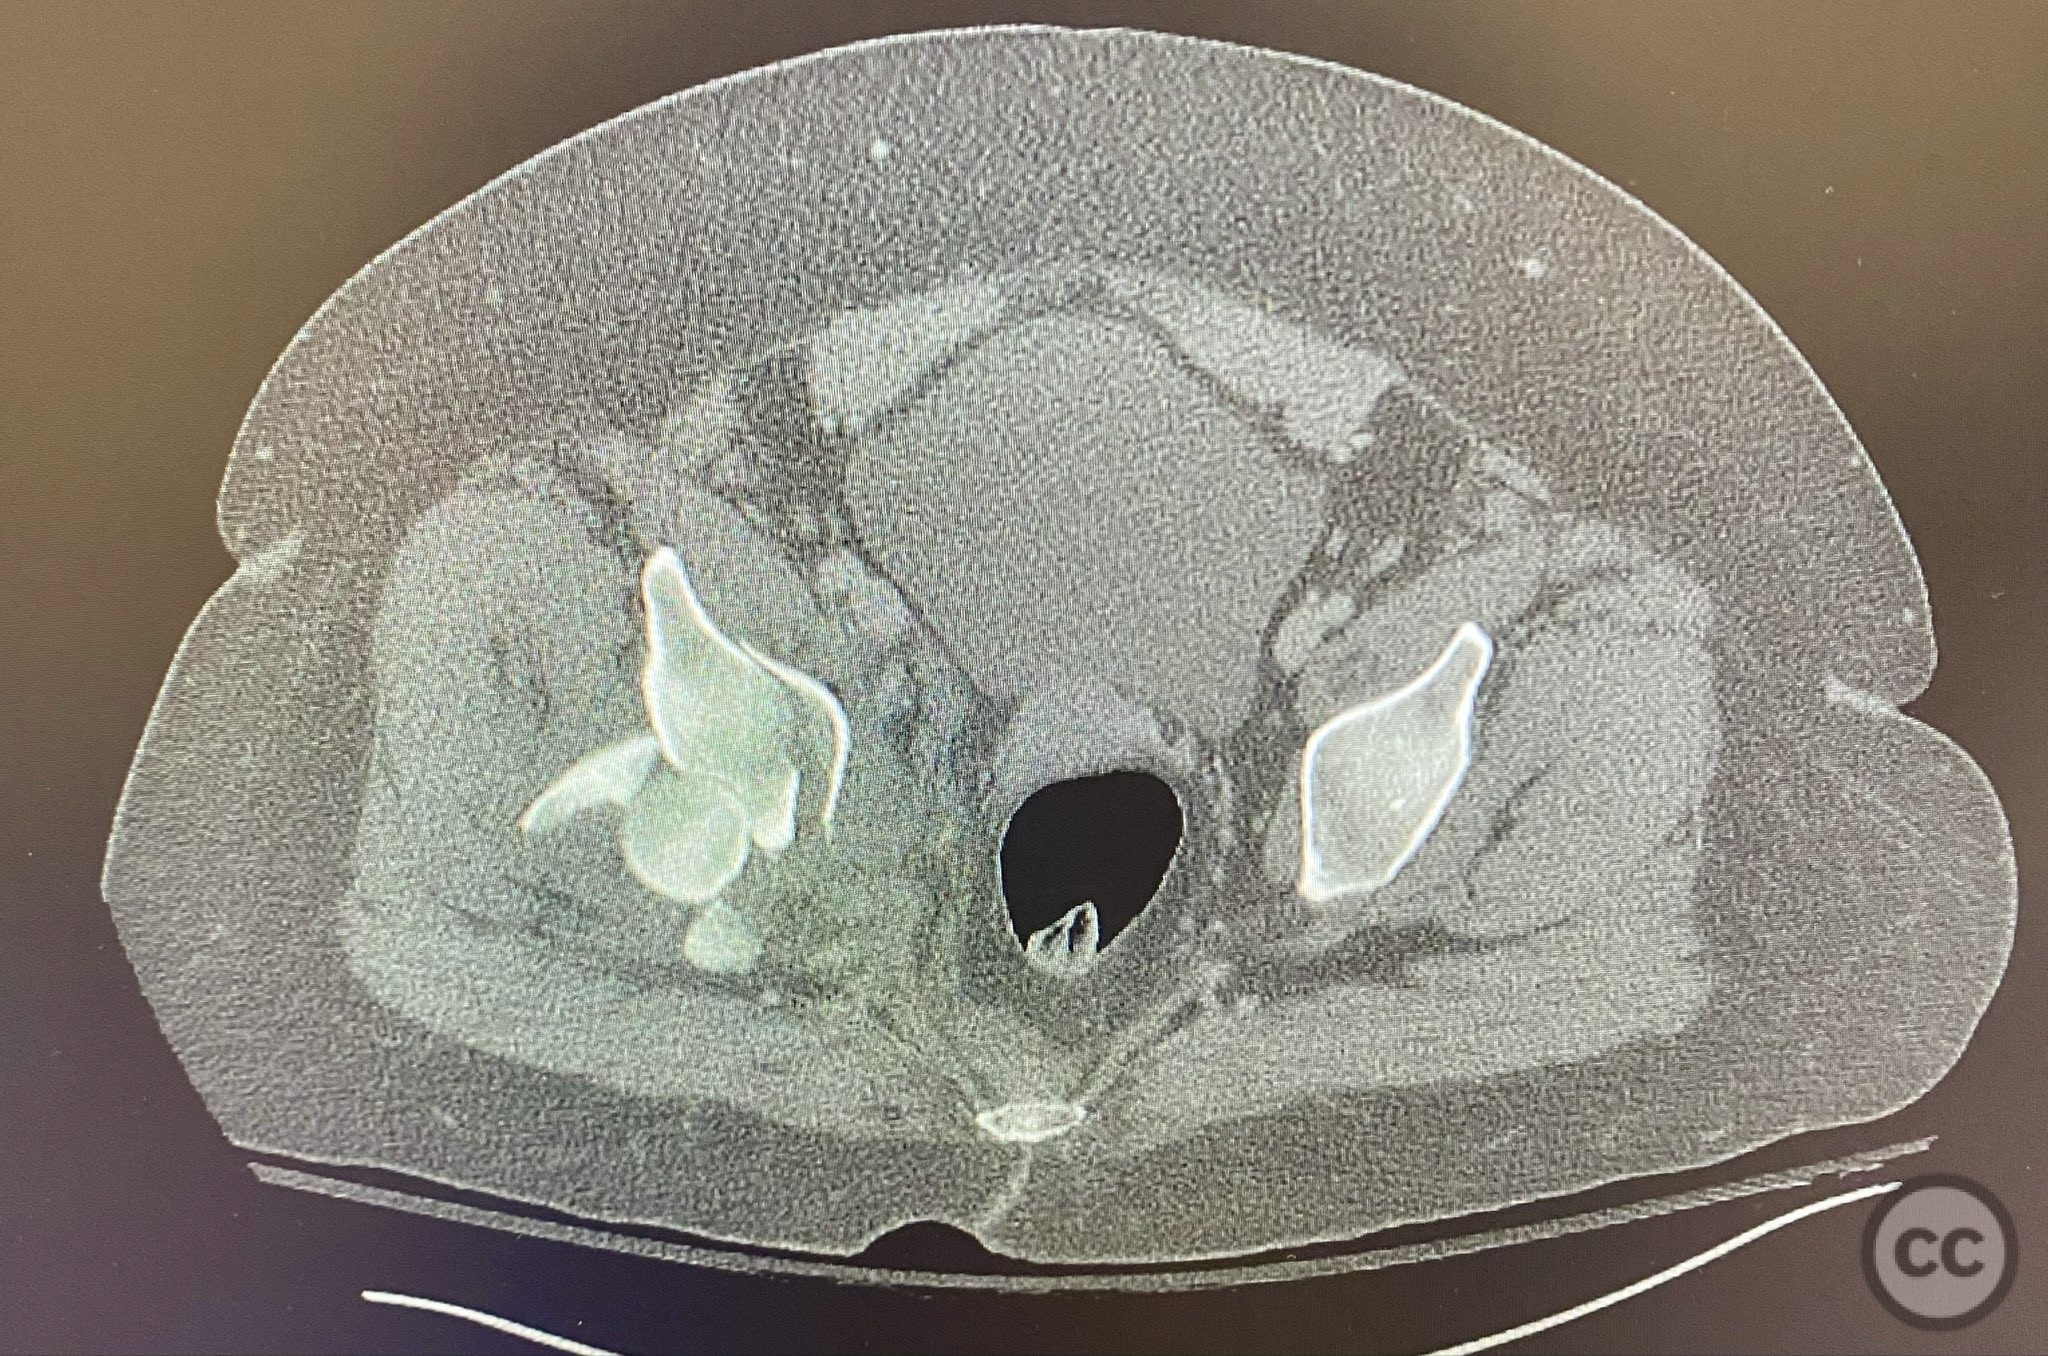

The transverse fracture was manipulated and temporarily stabilized using a reduction clamp applied across the fracture plane. Under biplanar fluoroscopic guidance, a cannulated cancellous lag screw was percutaneously inserted to achieve interfragmentary compression across the transverse component. The reduction clamp was then removed. Posterior wall fragments were anatomically reduced and stabilized with contoured buttress plates spanning both the posterior wall and providing additional stabilization to the transverse component. Postoperative CT confirmed satisfactory reduction and fixation of both acetabular columns and restoration of articular congruity.